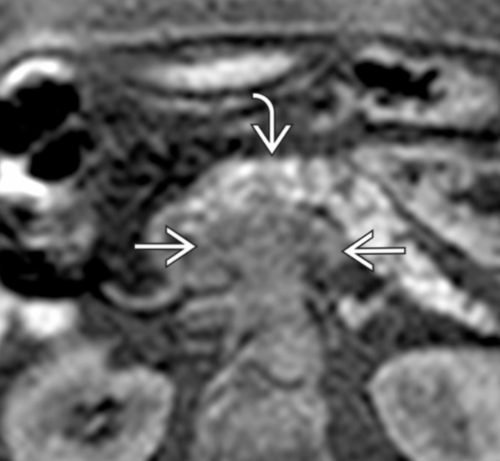

• Infiltration de la lame rétroporte (entre l’AMS et l’uncus)

Lame rétroporte

30ae661f336d9a14a72e6852301c9dff.png22273c6770a8130d84ddd7d72bac2330.png